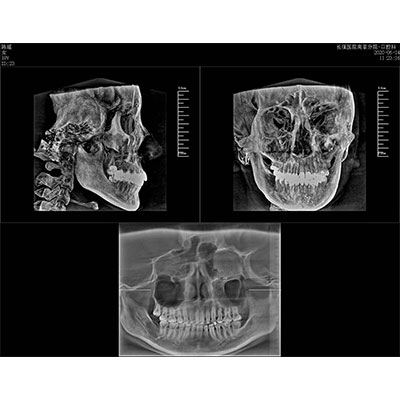

該款牙科CBCT產(chǎn)品采用動態(tài)平板探測器,獲得三維圖像的同時還具有數(shù)字化全景功能,廣泛應(yīng)用于口腔頜面外科、正畸科、正頜外科、種植科、牙體科、顳下頜關(guān)節(jié)科等術(shù)前術(shù)后。

可同時觀察軸向面、冠狀面和矢狀面圖像,方便臨床診斷。